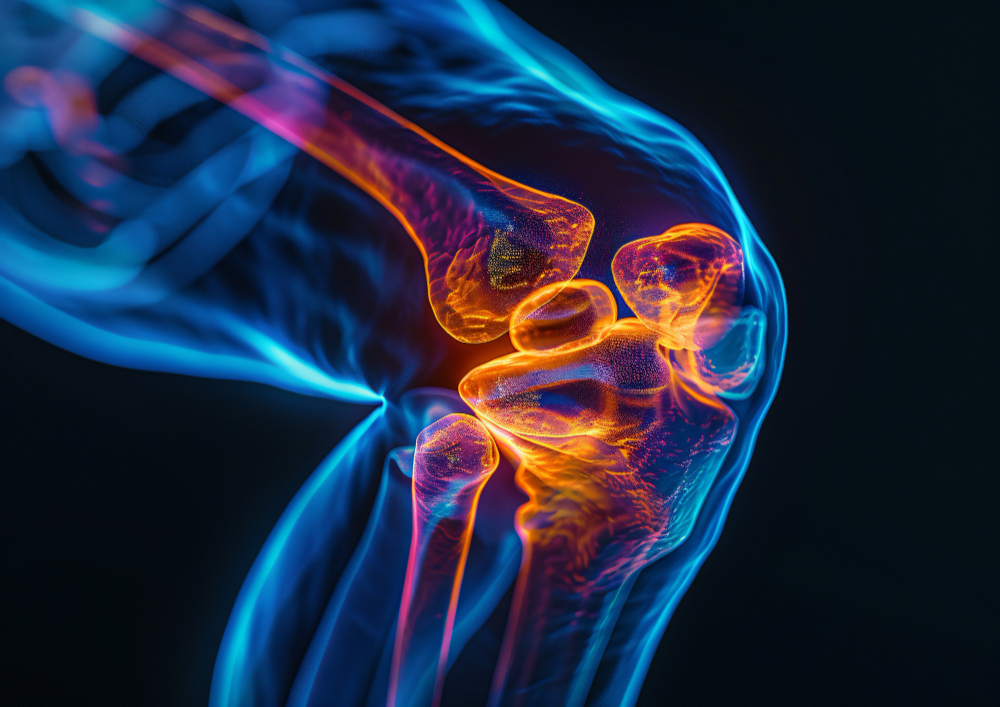

The hip replacement procedure typically takes 1 to 2 hours. Patients are usually required to stay in the hospital for 4 to 7 days post-surgery. Recovery time varies but most patients begin walking with support within 24 to 48 hours. Full recovery may take 6 to 12 weeks, depending on the patient’s age, health condition, and rehabilitation progress. Knee replacement surgery in India.

Rehabilitation and physiotherapy play a crucial role in ensuring the success of the surgery. Regular exercise, a healthy diet, and lifestyle changes are advised to improve joint function and extend the life of the implant, which typically lasts 15 to 20 years.

As with any major surgery, hip replacement carries some risks, such as infection, blood clots, dislocation, and implant wear. However, with experienced surgeons and proper medical care, complications are rare and manageable.